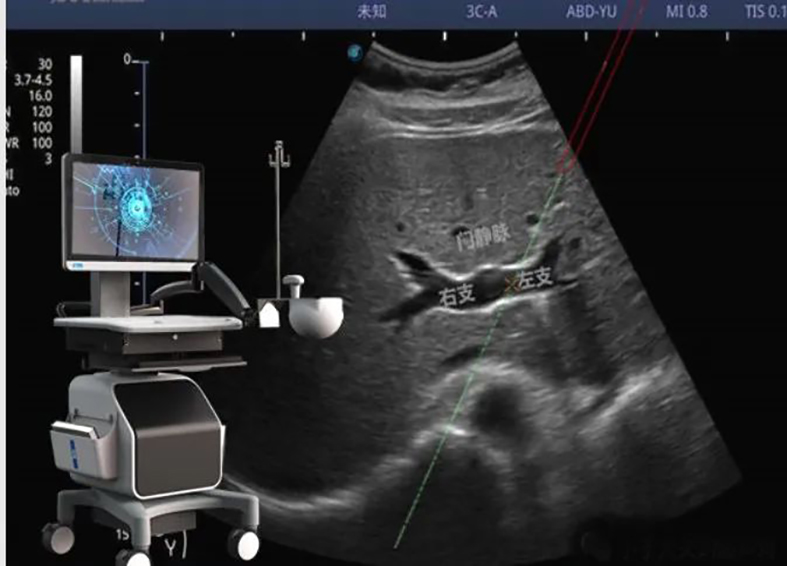

超声用电磁定位穿刺引导TIPS术将超声图像与电磁信号相融合,突破传统超声引导必须在平面内或平面外穿刺制约,能够在任意位置、任意角度、任意平面穿刺靶点,真正实现实时三维穿刺导航。更为重要的是,该技术具有我国自主知识产权。冯对平介绍,该新型穿刺引导技术能够大大降低TIPS术中门静脉穿刺难度,提高TIPS手术成功率,同时术者及患者受X线辐射时间也明显缩短,值得进一步推广应用。